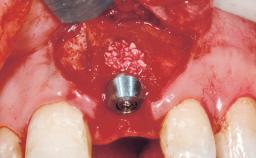

Immediate Flapless Placement of an Implant in a Maxillary Left Central Incisor Site

A 29-year-old female patient presented for treatment to replace the upper left central incisor tooth with an implant- supported restoration. The tooth had been intermittently symptomatic for the previous 12 months. The tooth had originally suffered trauma about 15 years previously. Several endodontic treatments had been performed, including an apicectomy procedure to retain the tooth. The patient was healthy and a non-smoker. She had reasonable expectations in regard to esthetic outcomes and the risk of marginal tissue recession following treatment. At medium smile, the gingival margins of the upper teeth were visible, with a display of 3 to 4 mm of the gingival margins. Gingival recession of tooth 21 and a discrepancy in the gingival levels between teeth 11 and 21 was observable during normal speech and smile.

| Placement Protocol | Immediate implant placement |